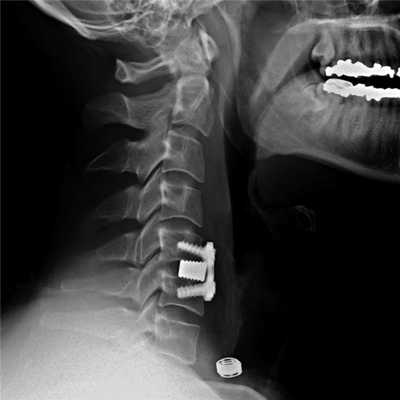

На шейных уровнях применяются и стабилизирующие тактики оперативных вмешательств, каждая из которых, кстати, может идти совместно и с другими видами операций. Наиболее популярные из стабилизирующих методов:

- - неподвижное соединение (сращивание) двух или более позвонков при их нестабильности;

Импланты шейного отдела позвоночника на рентгене.

Если клиника симптомов не поддается консервативной терапии или неинвазивные способы не могут быть задействованными ввиду сильно прогрессирующего стеноза, назначается операция. Вмешательство предполагает использование декомпрессионной ламинэктомии под общим наркозом. При комбинированной проблеме, например, вместе с грыжей, ее сочетают с микродискэктомией и спондилодезом. При спондилодезе осуществляют скрепление смежных позвонков металлическими фиксаторами (стержнями, пластинами, крючками и пр.), установку межтеловых имплантатов или вживление костного трансплантата с металлической гильзой.